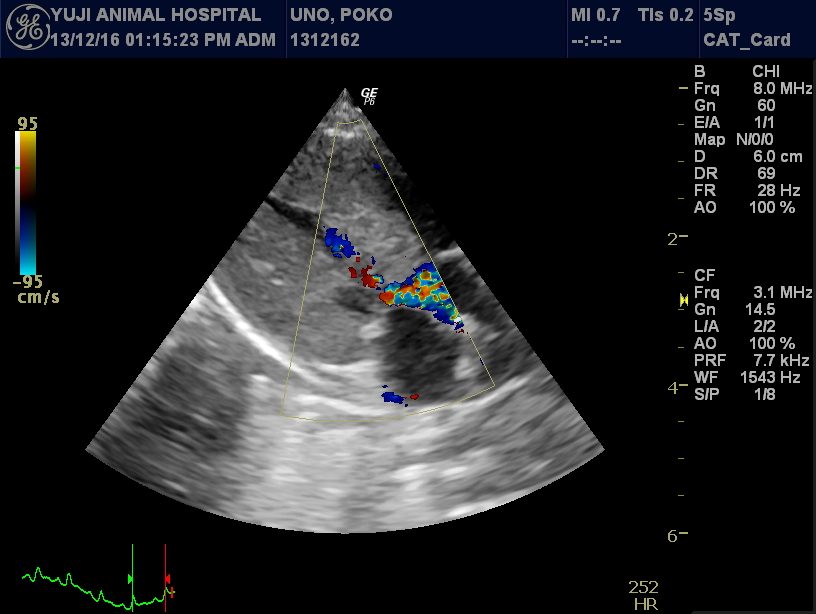

心エコー検査:

この病気の診断において最も重要な検査です。

心臓の筋肉が厚くなっていないかを計測し、内腔(LVIDd)が狭くなっていないかも計測します。また収縮機能の亢進(FSの上昇)や、カラードプラにより拡張機能の障害(E派の上昇)も診断します。弁(心臓の部屋と部屋の扉)が引っ張られたり、逆流がおきていないか(SAM)も同時に確認します。